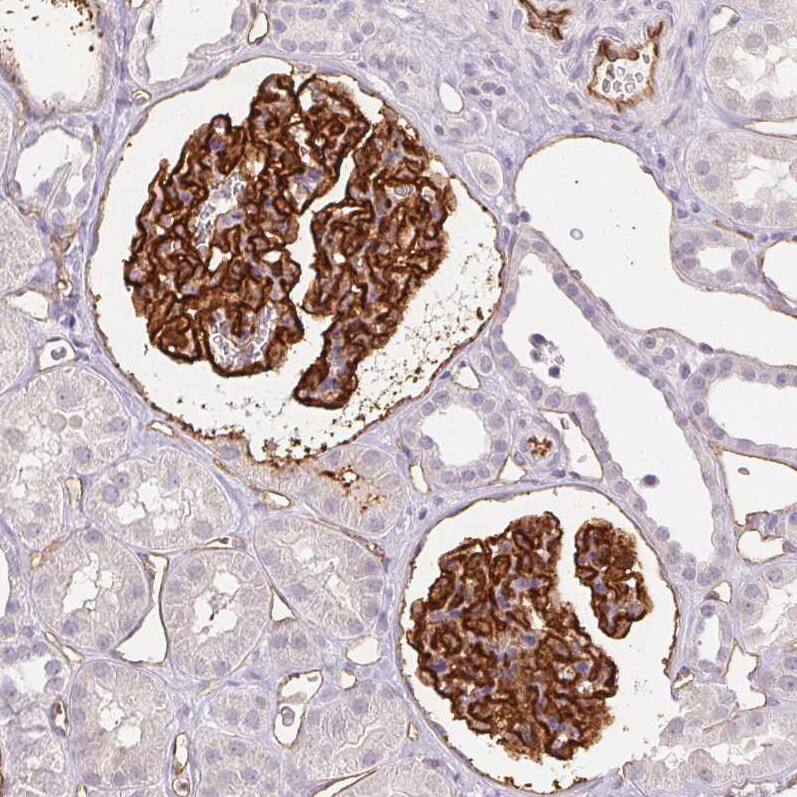

Staining of human kidney shows strong membranous positivity in cells in glomeruli, as well as endothelial cells.